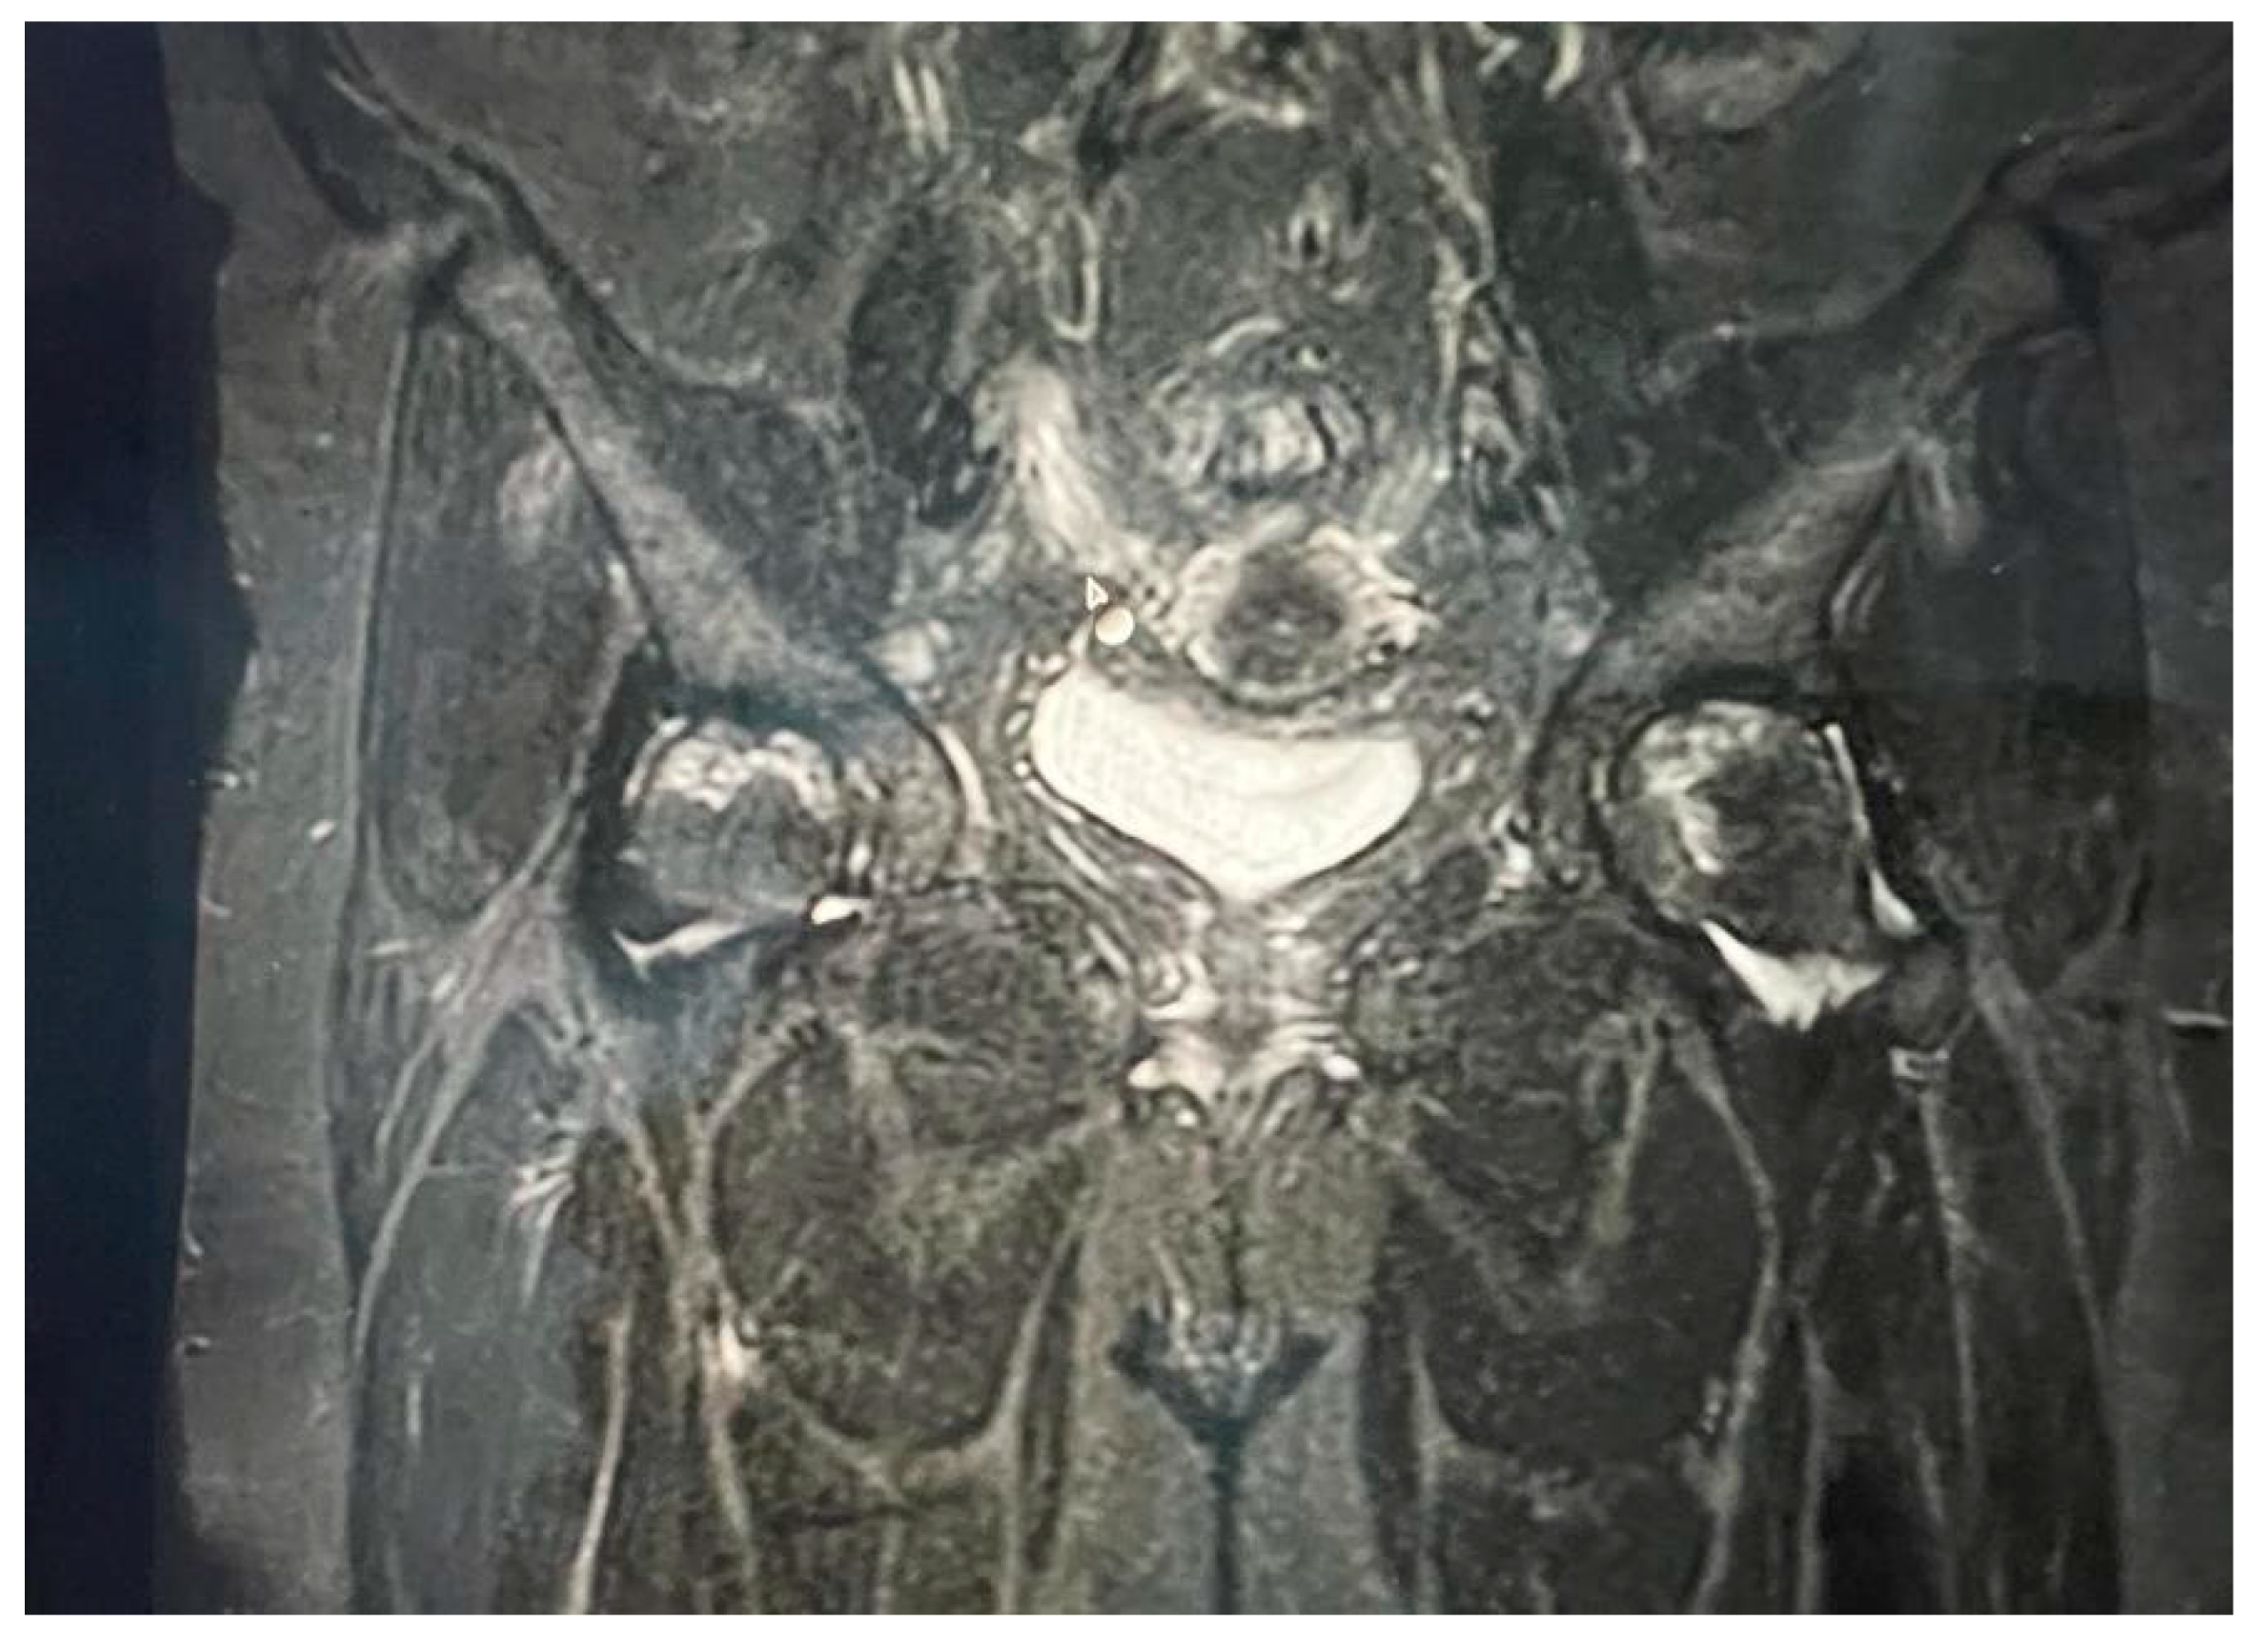

By adhering to stringent inclusion criteria and rigorous diagnostic standards, we sought to enhance the accuracy and validity of our analysis. This meticulous approach not only bolstered the credibility of our findings but also facilitated a comprehensive exploration of the intricate relationship between COVID-19 and avascular necrosis of the femoral head (Figure 1 and Figure 2).

Figure 1. Bilateral hip MRI with avascular necrosis.